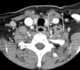

Sternocleidomastoid muscle hypertrophy

Spasmodic torticollis is an extremely painful chronic neurological movement disorder causing the neck to involuntarily turn to the left, right, upwards, and/or downwards. The condition is also referred to as "cervical dystonia". [Source: Wikipedia ]